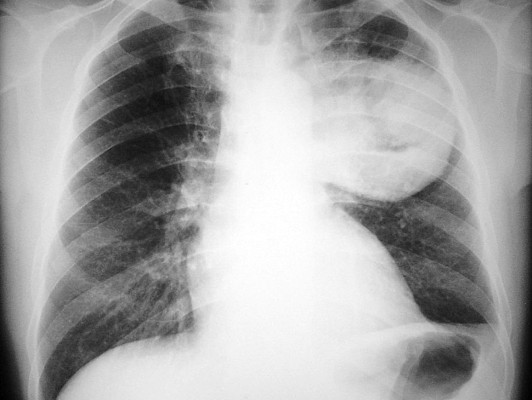

Lo que podría aumentar riesgo de cáncer de pulmón

Las personas que fuman o tienen cáncer de pulmón deberían pensar dos veces antes de tomar suplementos vitamínicos, según un estudio divulgado el miércoles que mostró que ciertos antioxidantes pueden impulsar el crecimiento de tumores malignos.

Los suplementos de vitaminas antioxidantes aceleran el desarrollo de las lesiones precancerosas y el cáncer de pulmón en etapa precoz, indicó este estudio sueco publicado en la revista médica estadounidense Science Translational Medicine, que aclara por primera vez este mecanismo.